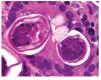

¿ Figura 3. Hematoxilina-eosina: Estrongiloidiasis gástrica.

¿ Figura 4. Hematoxilina-eosina: Estrongiloidiadis gástrica.

Mujer de 74 años de edad, residente del Distrito Federal, con antecedente de esclerodermia y cirrosis biliar primaria en tratamiento con ácido ursodeoxicólico. Inició ocho días previos a su ingreso con dolor abdominal epigástrico, náusea, distensión abdominal y melena. A la exploración física se encontró con signos vitales normales, mucosas pálidas, peristaltismo disminuido, sin otros hallazgos relevantes. Los exámenes de laboratorio mostraron hemoglobina 10.6 gr/dL, hematocrito 31%, leucocitos totales 8700 células/dL (4% de eosinófilos). Se le realizó endoscopia de tubo digestivo, que evidenció esofagitis erosiva grave, gastropatía eritematosa petequial, múltiples úlceras gástricas de 10 mm de diámetro con base de fibrina (Figura 1) y duodenitis erosiva (Figura 2). Se tomaron biopsias de los bordes de las ulceras y se envió en formol a estudio histopatológico que informó estrongiloidiasis gástrica, con inflamación crónica y aguda sin Helicobacter pylori (Figuras 3 y 4).